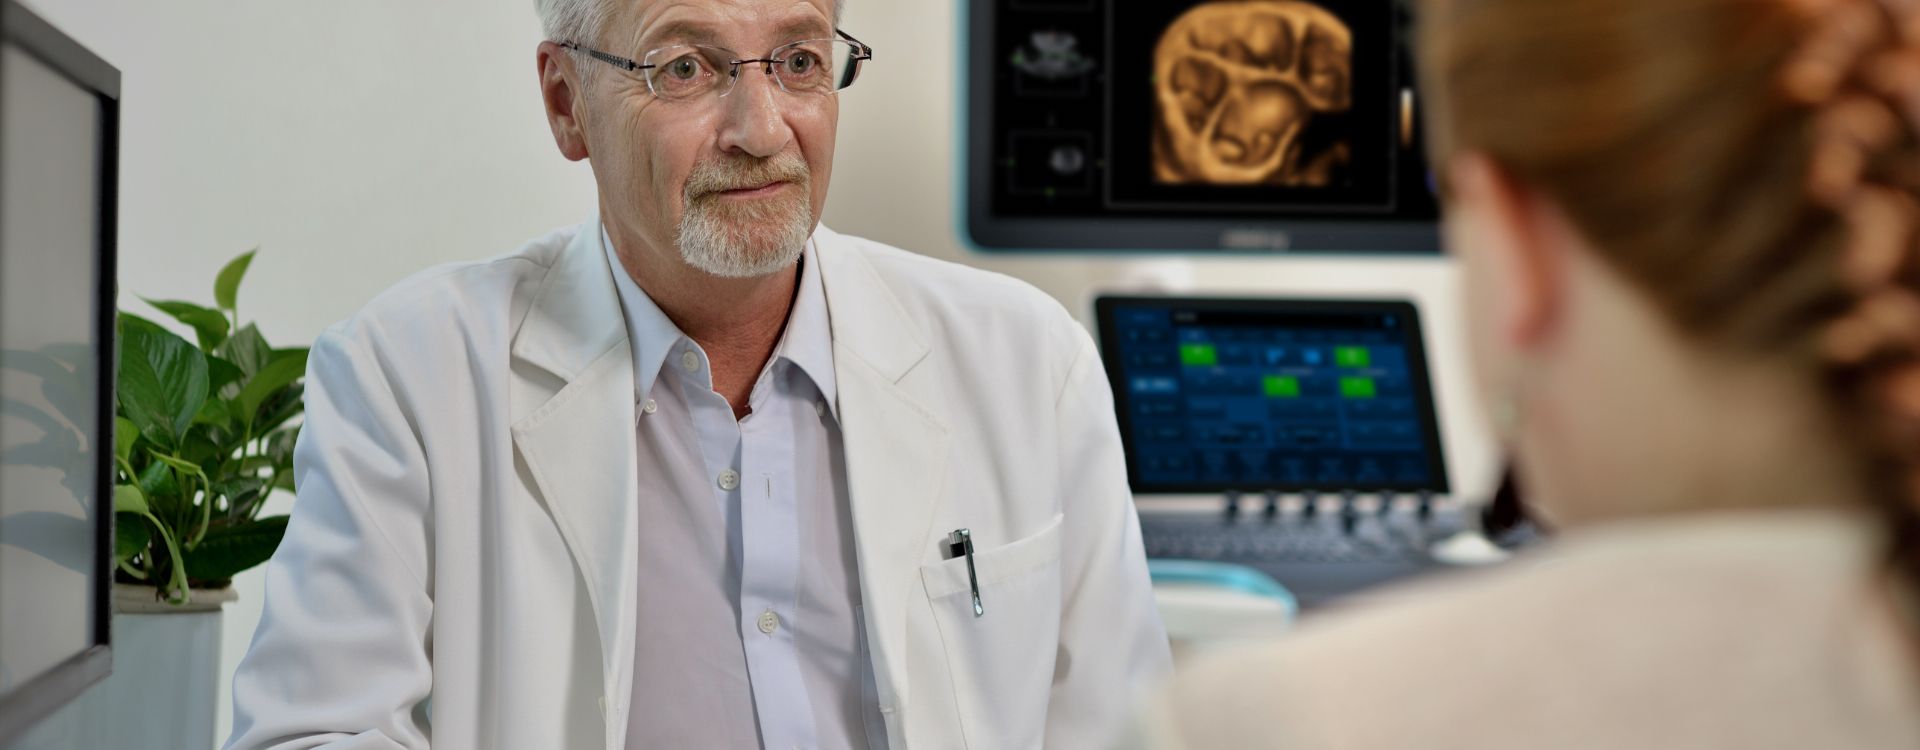

????? Resona ?? ?? ???? ???? ??? ?? ??? ? ???? ??? ?? ??? ?? ???? ?? ???? ???? ?? ? ?? ??? ??? ? ??? ?????.

???? ?? ??? ???? ???? ???? ???? ?? ?? ????? ????.

????? Resona ?? ?? ???? ???? ??? ?? ??? ? ???? ??? ?? ??? ?? ???? ?? ???? ???? ?? ? ?? ??? ??? ? ??? ?????.